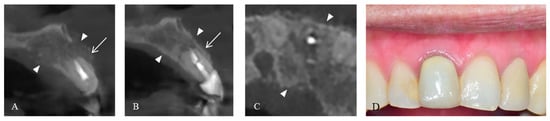

2. Case Presentation